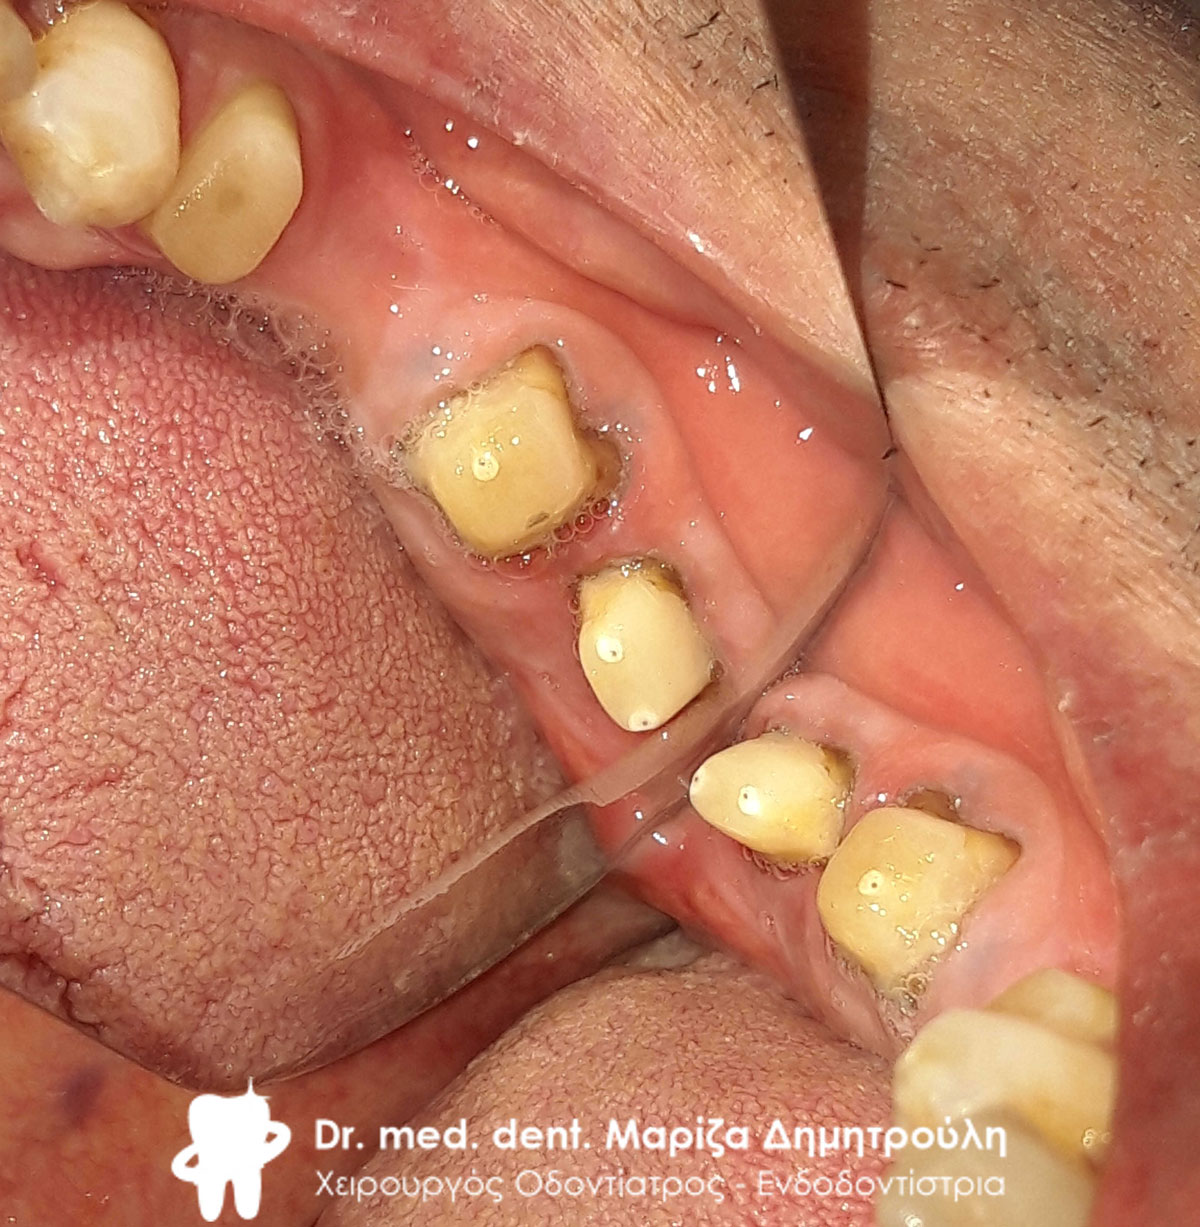

Αρχική κλινική εικόνα της αριστερής πλευράς της κάτω γνάθου

Αρχική κλινική εικόνα της αριστερής πλευράς της κάτω γνάθου

Αρχική κλινική εικόνα της αριστερής πλευράς της κάτω γνάθου

Αρχική κλινική εικόνα της αριστερής πλευράς της κάτω γνάθου

Αρχική κλινική εικόνα της αριστερής πλευράς της κάτω γνάθου